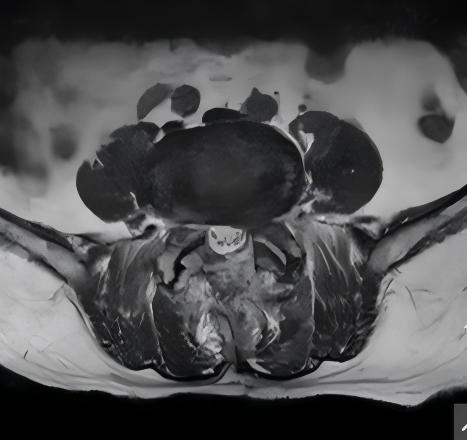

术后

术前